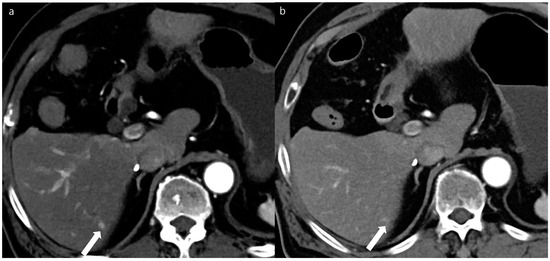

Figure 3. A 53-year-old man with a 2 cm sized hepatocellular carcinoma at segment 2 of the liver (arrows). Arterial phase (a), portal phase (b), and delayed phase (c) images of a standard-dose CT using hybrid iterative reconstruction show a well-enhancing nodule in the arterial phase (a), with washout on the portal phase (b) and the delayed phase (c).